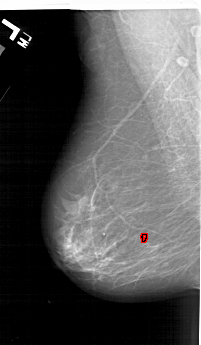

A_1124_1.LEFT_CC

LEFT_CC LINES 6331 PIXELS_PER_LINE 3376 BITS_PER_PIXEL 12 RESOLUTION 43.5 OVERLAY

FILE: A_1124_1.LEFT_CC.OVERLAY

TOTAL_ABNORMALITIES 1

ABNORMALITY 1

LESION_TYPE CALCIFICATION TYPE PLEOMORPHIC DISTRIBUTION LINEAR

ASSESSMENT 4

SUBTLETY 1

PATHOLOGY MALIGNANT

TOTAL_OUTLINES 1

BOUNDARY